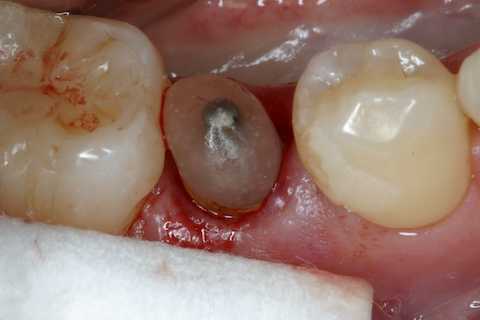

今日の抜歯再植術シリーズ39.2 2025.11.15